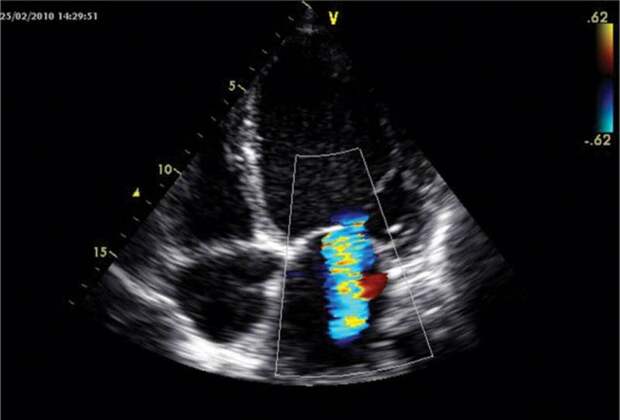

- Ультразвуковое исследование сердца.